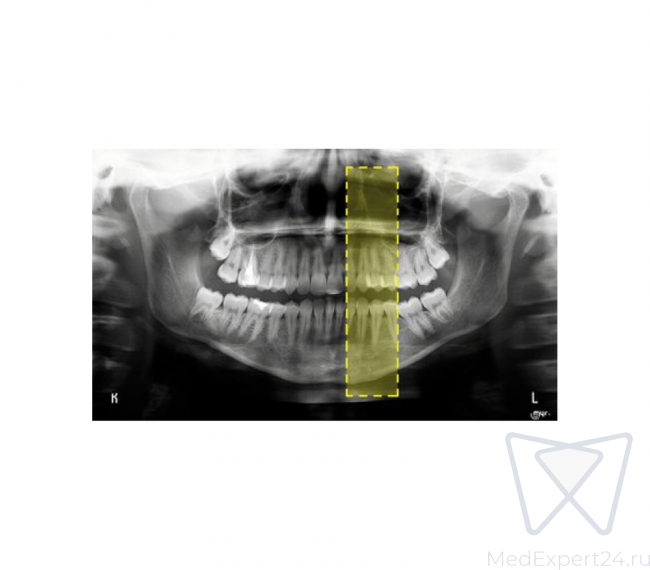

- Искусственный интеллект;

- Построение 3D изображения;